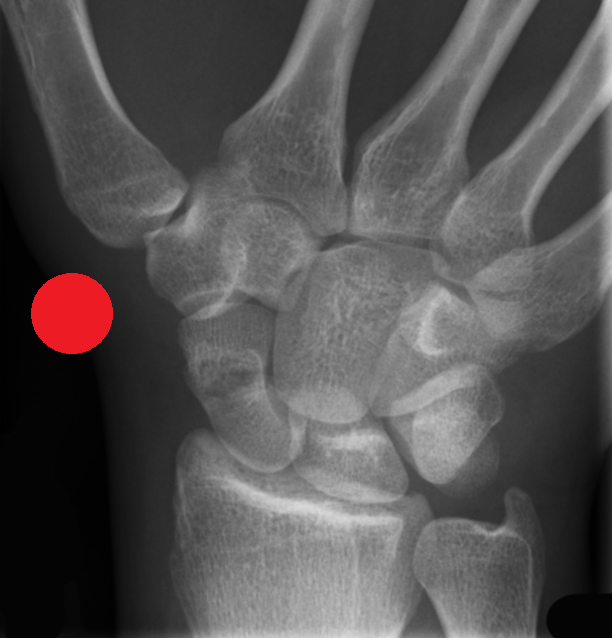

MSK CASES

www.mskradiology4u.co.uk

Red Dot X-Ray Interpretation Course (Two Days Online)

This TWO DAY comprehensive Red Dot X-Ray Interpretation Course is designed for Advanced Clinical Practitioners working in acute MSK care, for example in A/E or minor injuries and who are seeking to enhance confidence and improve their diagnostic assessment and accuracy.  Advanced Clinical Practitioners eligible for attendance include Advanced Nurse Practitioners and Advanced Physiotherapist Practitioners.

The course focuses on the identification and escalation of suspected pathology, fractures, or other deviations from normal imaging appearances. Participants will build robust knowledge and improve their ability to flag potentially critical findings.

The course focuses on improving the skills needed to identify a range of acute pathologies on x-rays, including fractures, dislocations, chest abnormalities and more. The course will improve patient safety by reducing missed urgent findings, especially whilst waiting for report completion.

• Improved identification of key radiographic features of common acute pathologies, eg. fractures, dislocations, pnemothorax.

• Improved ability to distinguish between normal anatomical variants and common pathological findings on Radiographs.